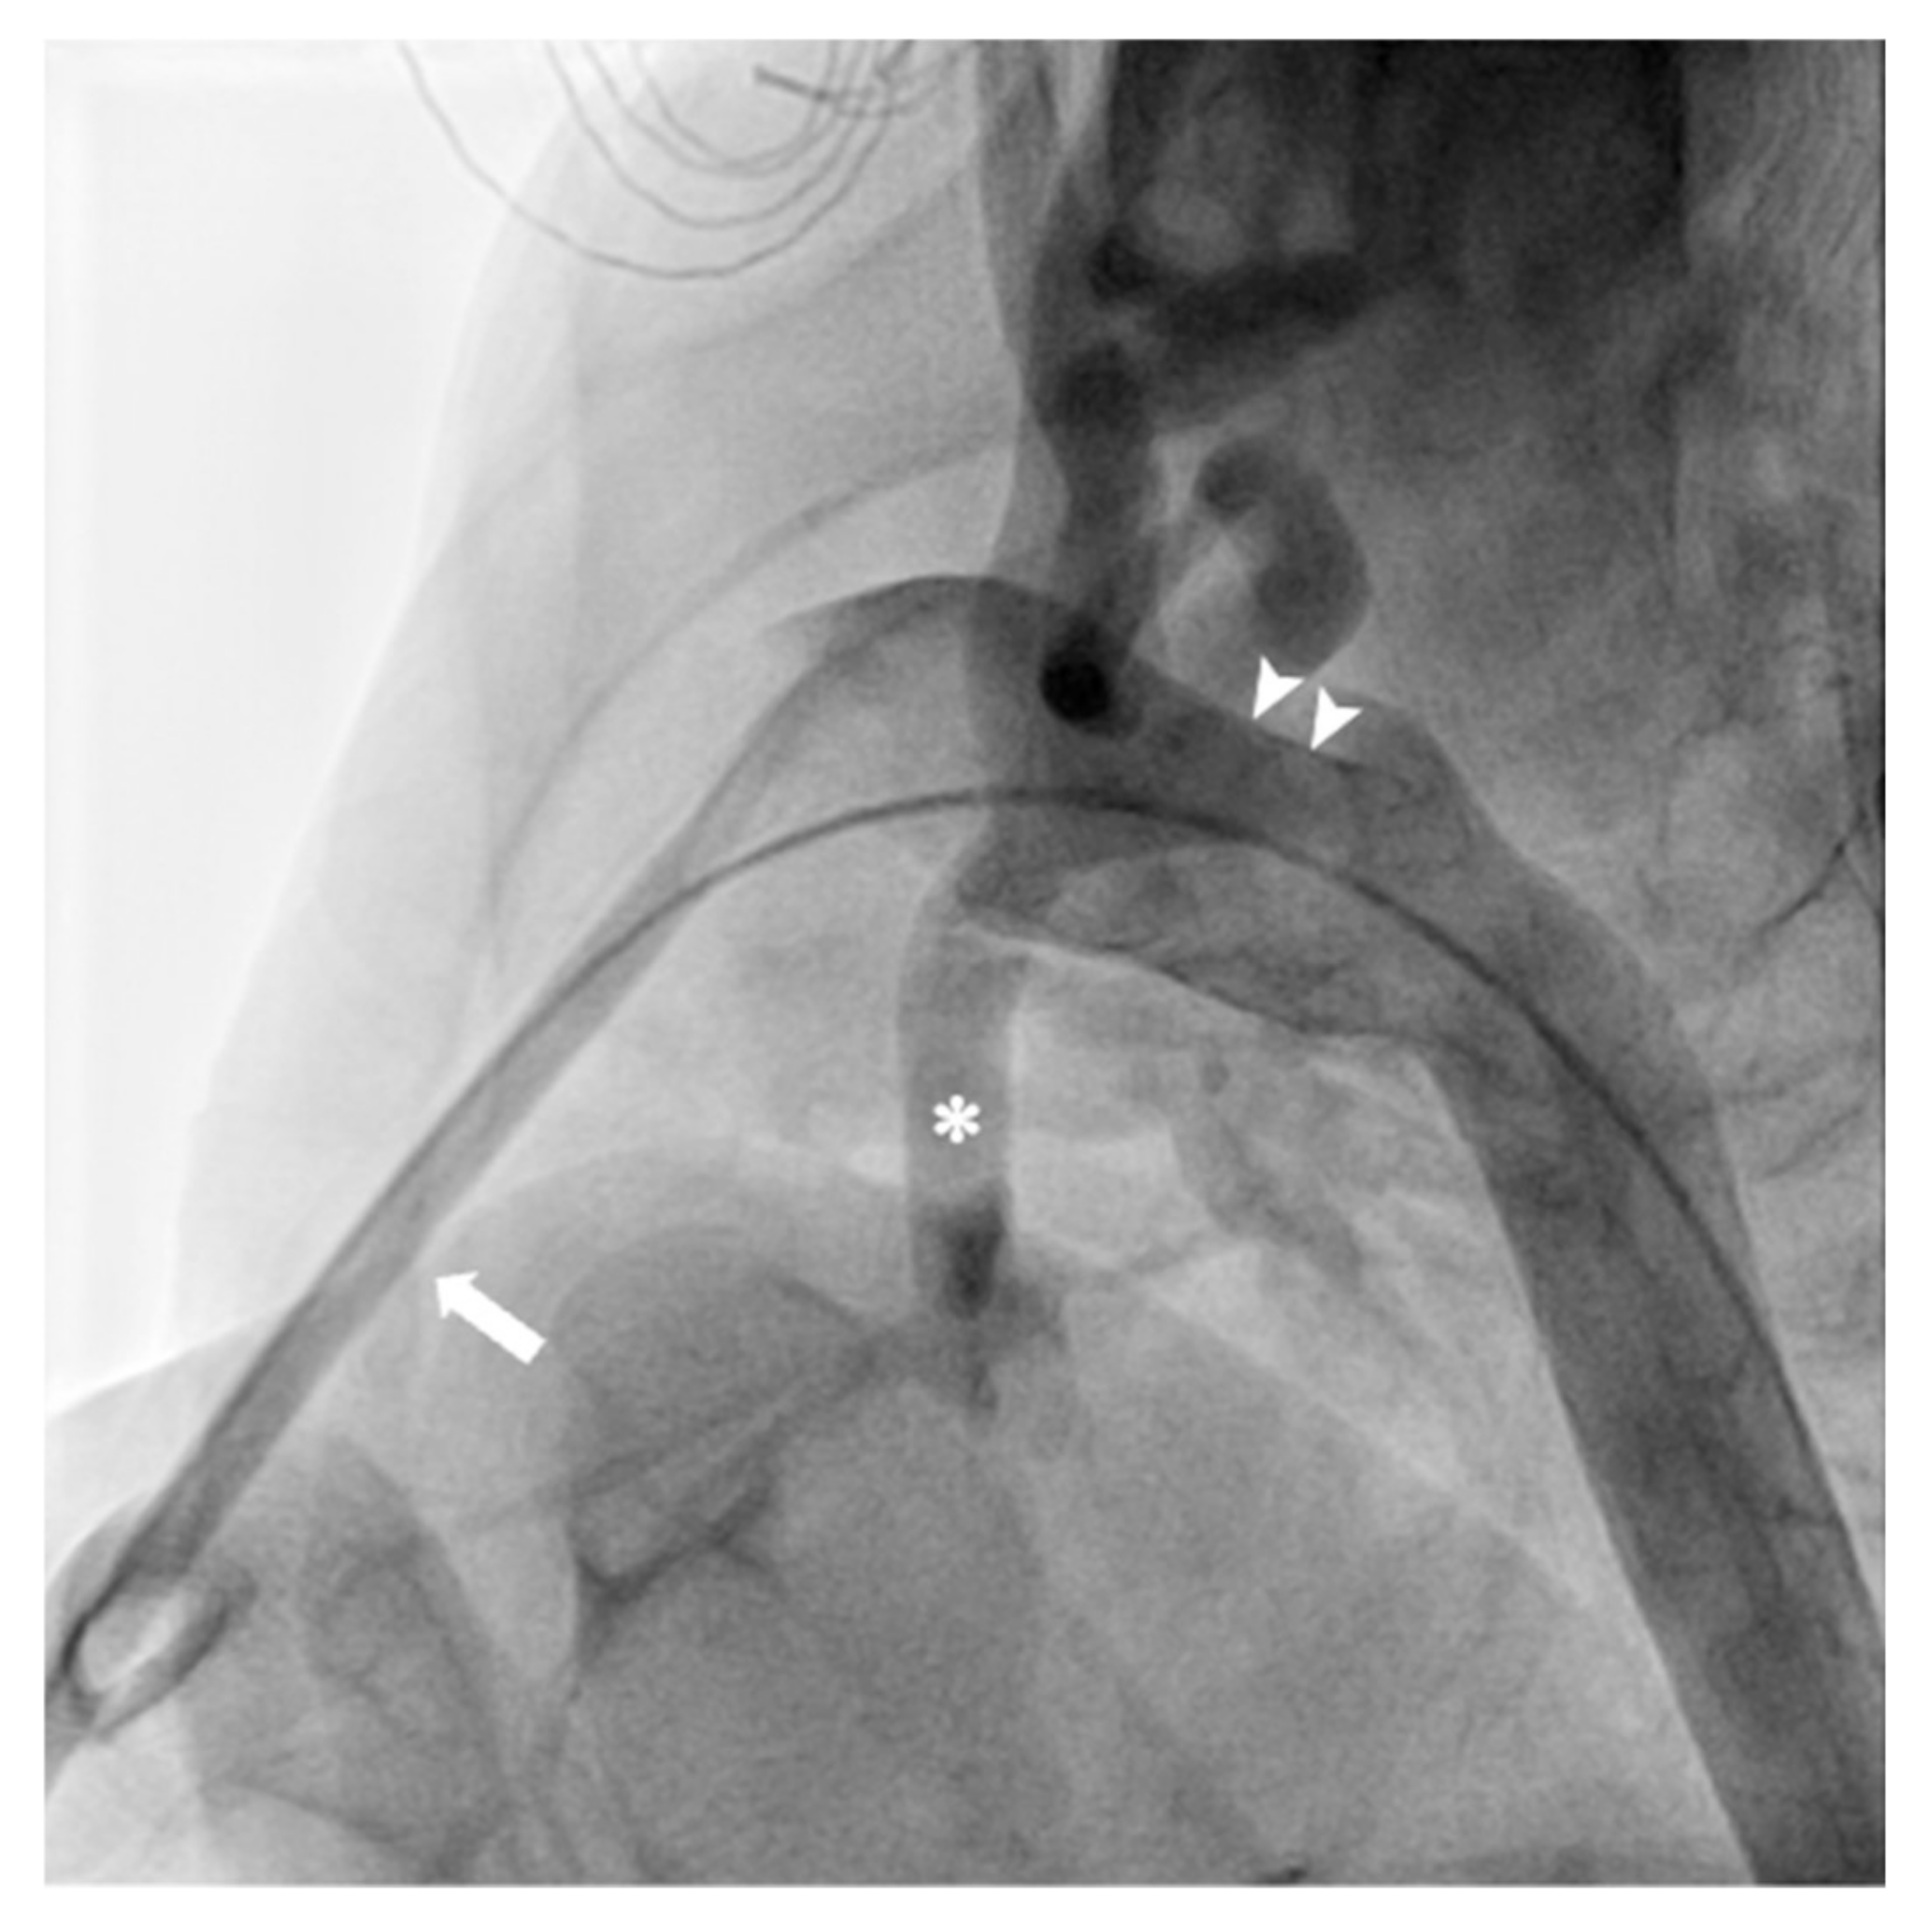

- Karamlou, T.; Bernasconi, A.; Jaeggi, E.; Alhabshan, F.; Williams, W.G.; Van Arsdell, G.S.; Coles, J.G.; Caldarone, C.A. Factors associated with arch reintervention and growth of the aortic arch after coarctation repair in neonates weighing less than 2.5 kg. J. Thorac. Cardiovasc. Surg. 2009, 137, 1163–1167. [Google Scholar] [CrossRef]

- Curzon, C.L.; Milford-Beland, S.; Li, J.S.; O’Brien, S.M.; Jacobs, J.P.; Jacobs, M.L.; Welke, K.F.; Lodge, A.J.; Peterson, E.D.; Jaggers, J. Cardiac surgery in infants with low birth weight is associated with increased mortality: Analysis of the Society of Thoracic Surgeons Congenital Heart Database. J. Thorac. Cardiovasc. Surg. 2008, 135, 546–551. [Google Scholar] [CrossRef]

- Garg, G.; Goyal, N.; Mandhan, G.; Sidana, P. Transfemoral balloon angioplasty of severe coarctation of aorta in 1200 g newborn. Ann. Pediatr. Cardiol. 2017, 10, 95–96. [Google Scholar] [CrossRef]

- Fiore, A.C.; Fischer, L.K.; Schwartz, T.; Jureidini, S.; Balfour, I.; Carpenter, D.; Demello, D.; Virgo, K.S.; Pennington, D.G.; Johnson, R.G. Comparison of angioplasty and surgery for neonatal aortic coarctation. Ann. Thorac. Surg. 2005, 80, 1659–1664; discussion 1664–1665. [Google Scholar] [CrossRef] [PubMed]

- Bouzguenda, I.; Marini, D.; Ou, P.; Boudjemline, Y.; Bonnet, D.; Agnoletti, G. Percutaneous treatment of neonatal aortic coarctation presenting with severe left ventricular dysfunction as a bridge to surgery. Cardiol. Young 2009, 19, 244–251. [Google Scholar] [CrossRef] [PubMed]

- Rothman, A.; Galindo, A.; Evans, W.N.; Collazos, J.C.; Restrepo, H. Effectiveness and safety of balloon dilation of native aortic coarctation in premature neonates weighing < or =2,500 grams. Am. J. Cardiol. 2010, 105, 1176–1180. [Google Scholar] [CrossRef] [PubMed]

- Sandoval, J.P.; Kang, S.L.; Lee, K.J.; Benson, L.; Asoh, K.; Chaturvedi, R.R. Balloon Angioplasty for Native Aortic Coarctation in 3- to 12-Month-Old Infants. Circ. Cardiovasc. Interv. 2020, 13, e008938. [Google Scholar] [CrossRef]

- Radtke, W.A.; Waller, B.R.; Hebra, A.; Bradley, S.M. Palliative stent implantation for aortic coarctation in premature infants weighing <1,500 g. Am. J. Cardiol. 2002, 90, 1409–1412. [Google Scholar] [CrossRef]

- Stegeman, R.; Breur, J.M.P.J.; Heuser, J.; Jansen, N.J.G.; de Vries, W.B.; Vijlbrief, D.C.; Molenschot, M.M.C.; Haas, F.; Krings, G.J. Primary coronary stent implantation is a feasible bridging therapy to surgery in very low birth weight infants with critical aortic coarctation. Int. J. Cardiol. 2018, 261, 62–65. [Google Scholar] [CrossRef]

- Mini, N.; Zartner, P.A.; Schneider, M.B.E. Stenting of critical aortic coarctation in neonates between 600 and 1,350 g. Using a transfemoral artery approach: A single center experience. Front. Cardiovasc. Med. 2022, 9, 1025411. [Google Scholar] [CrossRef]

- Gorenflo, M.; Boshoff, D.E.; Heying, R.; Eyskens, B.; Rega, F.; Meyns, B.; Gewillig, M. Bailout stenting for critical coarctation in premature/critical/complex/early recoarcted neonates. Catheter. Cardiovasc. Interv. 2009, 75, 553–561. [Google Scholar] [CrossRef]

- Sallmon, H.; Berger, F.; Cho, M.Y.; Opgen-Rhein, B. First use and limitations of Magmaris® bioresorbable stenting in a low birth weight infant with native aortic coarctation. Catheter. Cardiovasc. Interv. 2019, 93, 1340–1343. [Google Scholar] [CrossRef]